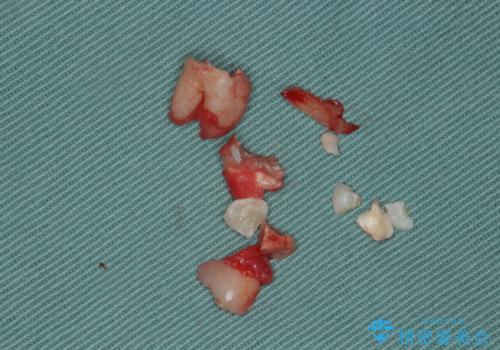

- 右上下親知らずを抜きたいとの事で来院。

レントゲンを確認したとこと完全埋伏歯でした。

CTで神経の位置などを確認し、抜歯術を行いました。

無事抜歯を行うことができました。